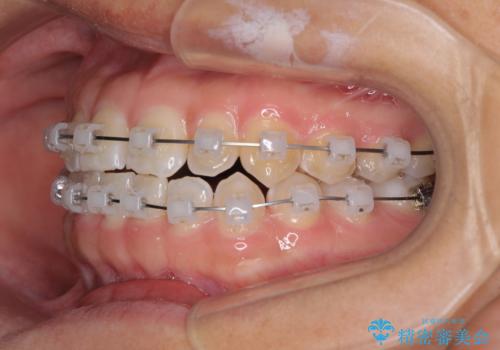

- 矯正装置

- クリアブラケット

下の前歯が上の前歯を突き上げるように咬合するため、咬み合わせの位置を改善しながら隙間を閉じていきました。

元々の歯並びが悪くなかったため、9ヶ月で綺麗に仕上がりました。